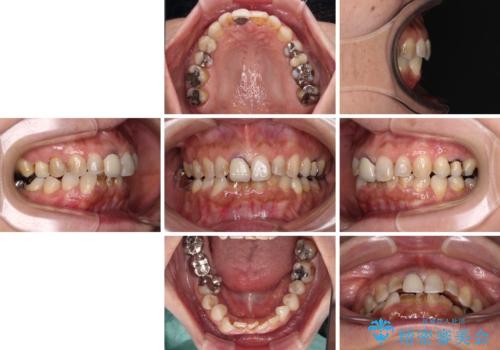

- 上下前歯のデコボコと、治療途中の歯を気にして来院された患者様です。

ご家族がインビザラインにて矯正治療を行っていたため、ご本人の希望によりインビザラインによるマウスピース矯正を行うこととしました。

根管治療が必要な歯は事前に処置を行った上で矯正治療を開始し、概ね歯列が整ったところでセラミッククラウンなどに置き換え、その後インビザラインを1セット使用して仕上げていくこととしました。